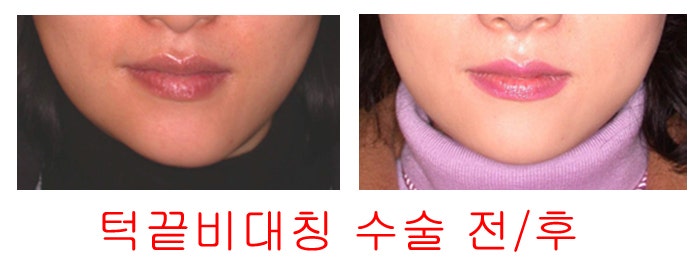

2. 이중 턱끝 축소 전진술(일명 샌드위치 절골술)

※또한! 더욱 중요한 점은

이 수술은 턱끝 수술과 함께

턱끝 비대칭!!도 동시에 치료할 수 있는 아주 큰 장점!!을 가지고 있습니다

※또한! 더욱 중요한 점은

이 수술은 턱끝 수술과 함께

턱끝 비대칭!!도 동시에 치료할 수 있는 아주 큰 장점!!을 가지고 있습니다